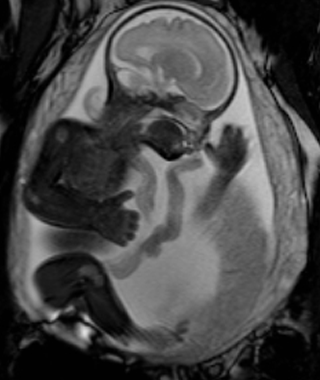

Anne adayları, bebeği ve kendisi için sorunsuz bir hamilelik istemektedir. Bu yüzden Fetal MR emar yaparak ileride oluşacak sorunlar veya oluşmuş olan sorunları görmek isterler.

Bebekte Fetal Mr, en çok fetüsün sinir sistemi rahatsızlıklarında kullanılmaktadır.

Bebeğin omurga, beyin kıvrımı, beyin boşluklarında genişleme, beyin gelişim fonksiyonları, kalıtsal beyin rahatsızlıkları patolojilerde Fetal Mr ile görüntüleme en iyi sonuçtur.

Ultrasonografi bebeğin yatış pozisyonunu eksi şekilde etkiler. Ama Fetal Mr de hiçbir sorun oluşmaz. Ayrıca bebeğin akciğer, karın boşluğu, kas-iskelet sisteminide incelemektedir.